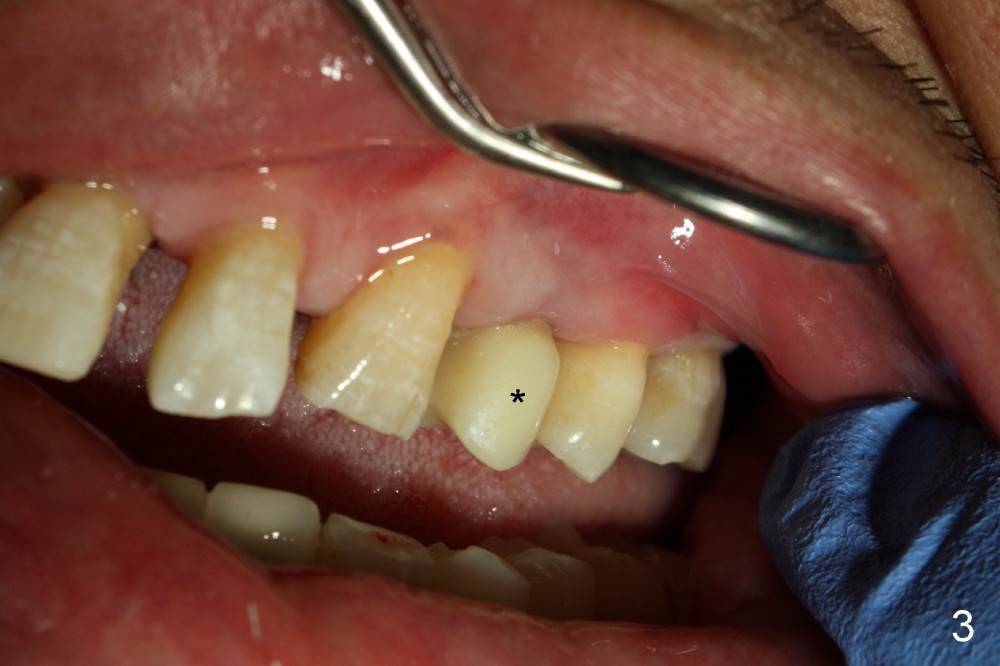

A temporary crown is fabricated for an upper left 1st premolar implant (Fig.1). There is a problem. The implant is placed a little too lingual (L). An extra ridge (R) is made buccal (B) to the buccal margin (M). Although the ridge improves cosmetics, it is not hygienic. Cement and food debris accumulates between the margin and ridge and it is difficult to clean. A smooth buccal margin is preferable (Fig.2). The temporary crown without ridge does not look too bad after cementation (Fig.3 *). The cervical area looks like a Class V defect. It will not get worse.